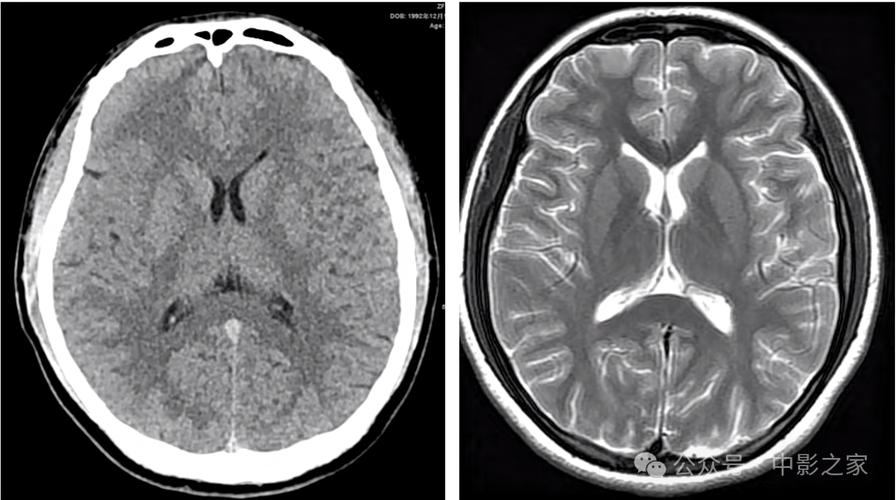

CT检查的“时间窗”限制

这是最关键的原因,CT对于脑梗死的诊断有一个非常明确的“时间窗”。

- 超早期(发病后6小时内):在这个阶段,脑细胞刚刚开始缺血,但细胞结构尚未发生不可逆的坏死,脑组织的含水量、密度等变化非常微小,常规CT扫描完全无法显示出异常,这个阶段的CT表现通常是“正常”的。

- 发病后6-24小时:缺血中心区域的脑细胞开始水肿,细胞坏死导致局部密度轻微降低,但这个密度变化非常细微,有经验的放射科医生可能会发现一些间接征象(如脑沟变浅、脑回模糊、豆状核边界模糊等),但常规CT仍可能报告为“未见明显异常密度灶”。

- 发病24-48小时后:脑细胞坏死和水肿达到高峰,梗死区域在CT上会显示出清晰的低密度灶,此时诊断就非常明确了。

- CT的局限性:CT主要看的是密度变化,对于早期细胞级别的缺血不敏感,而磁共振成像,特别是DWI序列(弥散加权成像),对早期脑缺血(发病后几分钟到几小时)就非常敏感,被称为诊断早期脑梗死的“金标准”。